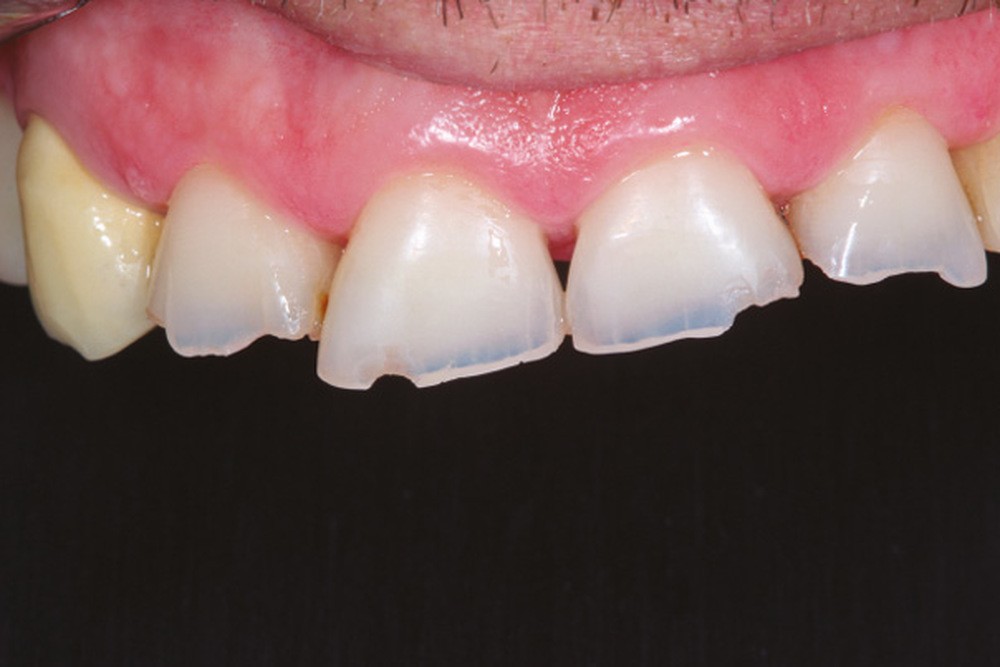

Le principe de protection mutuelle implique que les dents postérieures protègent les antérieures lors de la mastication. Des extractions non compensées de molaires, par exemple, entraîneront une hypersollicitation des antérieures et une usure importante du fait du principe de calage ainsi qu’un risque de perte de dimension verticale (fig. 10 à 13).